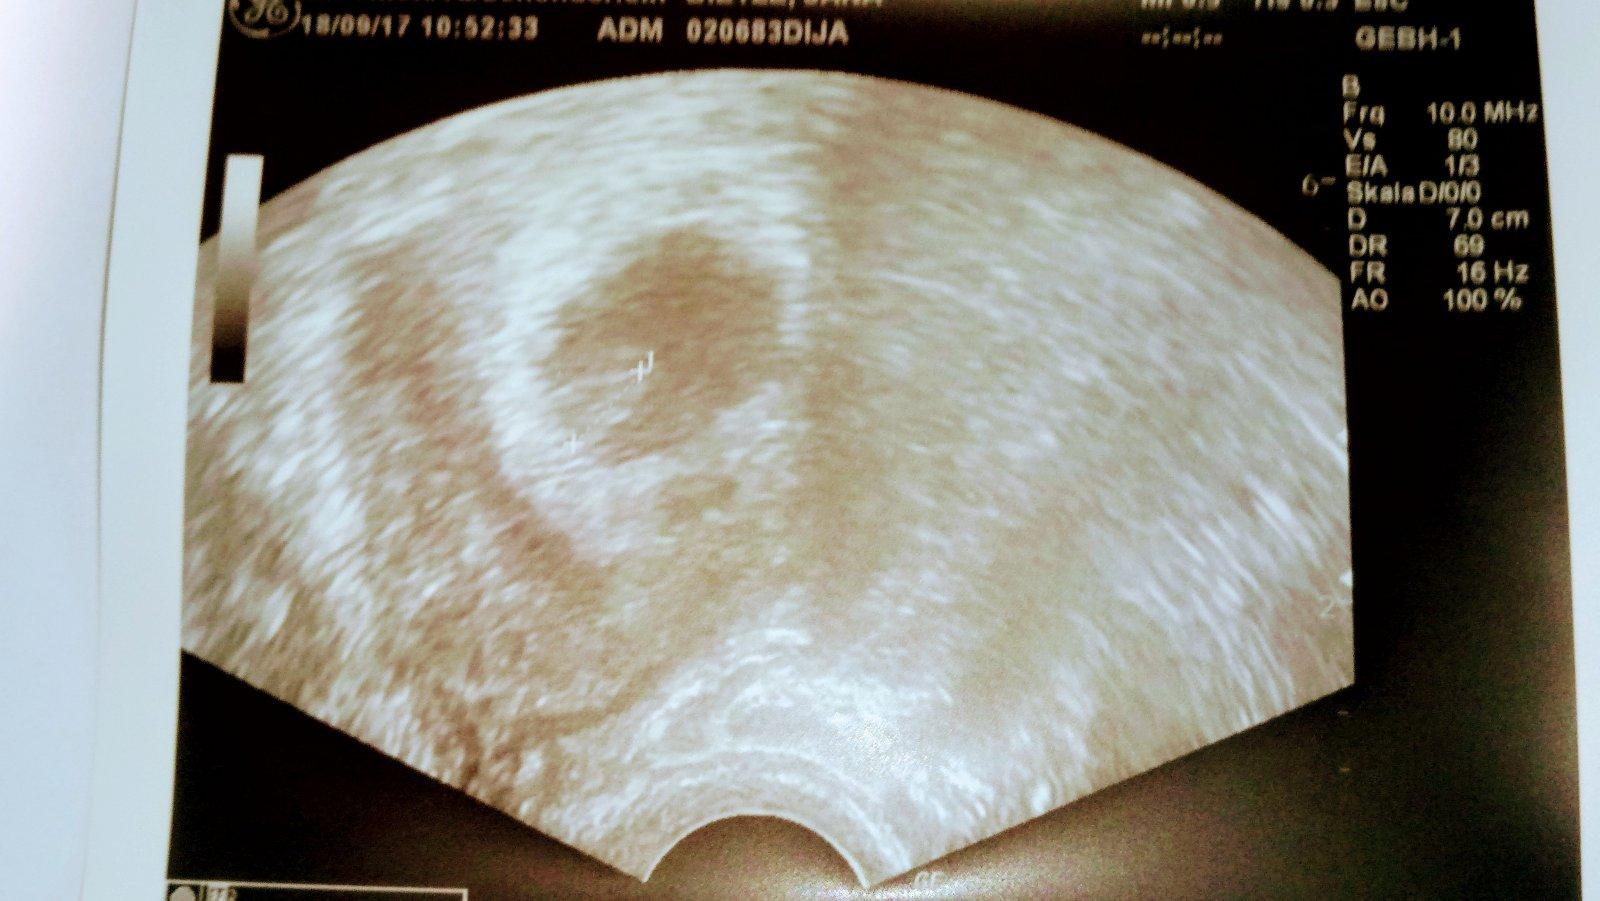

Tak jsme v poradku dnes 7+0 podle ultrazvuku. 6+6a srdicko tluce 😍

Jsme v poradku dnes 7+0 podle ultrazvuku 6+6 a srdicko tluce

@janapuma dekuji jak jsem slibila dala jsem foto a ted vas uz budu Jen sledovat

@tynka07 Juuu dekuji neboj urcite se taky brzy zadari jak jsi chtela dala jsem vam fotku z ultrazvuku a ted vas budu uz jen sledovat a vsem moc drzet palecky